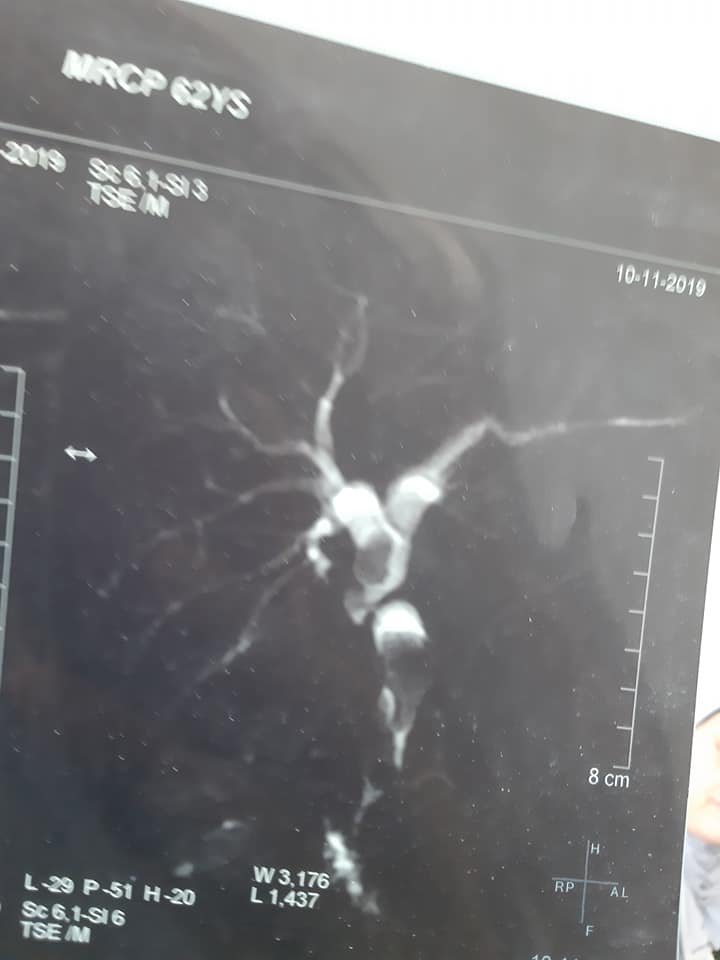

هذه صور رنين مغناطيسى علي القنوات المرارية لحالة تم لها إجراء عملية استئصال المرارة بالجراحة منذ ٢٠ سنة في مستشفى آخر وقد حدث اصابة جزئية في جدار القناة المرارية وقد وضع الجراح المعالج للحالة في ذلك الوقت أثناء العملية قسطرة في القناة المرارية لتصريف السائل المراري وقد حدث ضيق شديد في القناة المرارية مع تكوين حصوات في القناةالمرارية وصفراء انسدادية بعد ٢٠ سنة من إجراء إستئصال المرارة .

وهذا يبين أنه حتي في حالة الإصابات الجزئية للقناة المرارية أثناء عملية استئصال المرارة بالمنظار أو الجراحة يحتاج المريض إلي متابعة طويلة الأجل وذلك للإكتشاف المبكر للضيق و الذي قد يحتاج إلى عملية اصلاح للقناة المرارية بتوصيلها بالأمعاء أو حسب مايراه الأطباء المتخصصون.

MRCP images showing late marked bile duct stricture after open cholecystectomy done 20 years ago in another Hospital. Partial biliary injury occurred during the operation as the Patient has mentioned and the surgeon managed the case at that time by inserting biliary tube drainage from the site of bile duct injury. postoperatively there was bile leak aroud the drains that resolved spontaneously after about one month. Recently the Patient developed obstructive jaundice and ascending cholangitis and presented to us for definitive management .

The message is that all cases with bile duct injury need long term follow up even after partial bile duct injury that has been managed by biliary tube drainage as bile duct stricture may occur slowly over a long time.

Early detection of iatrogenic biliary stricture is essential and defintive biliary Reconstruction may be needed even many years after the previous biliary procedure.